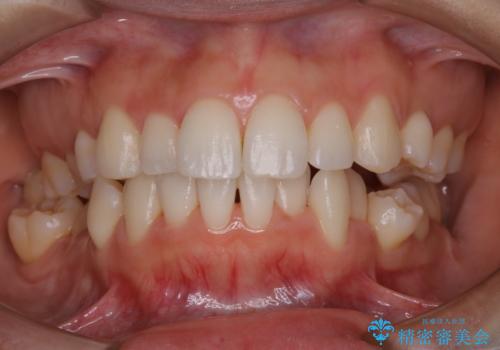

- しばらく来院できなかったため、全体的にチェックとクリーニング希望でした。PMTC60分コースを行いました。

歯にステイン(着色)や歯石などが付着していると、汚れなのか虫歯なのかの判別が分かりにくく、正確な診断ができないことがあります。

そのため、定期的に専門的な機械や材料を使用したクリーニング(PMTC)をすることで、ご自身本来の歯の状態となります。より、健康なお口の維持をするためには、痛みや症状などが無くてもPMTCを行いお口の中の環境を綺麗にすることがおすすめです。